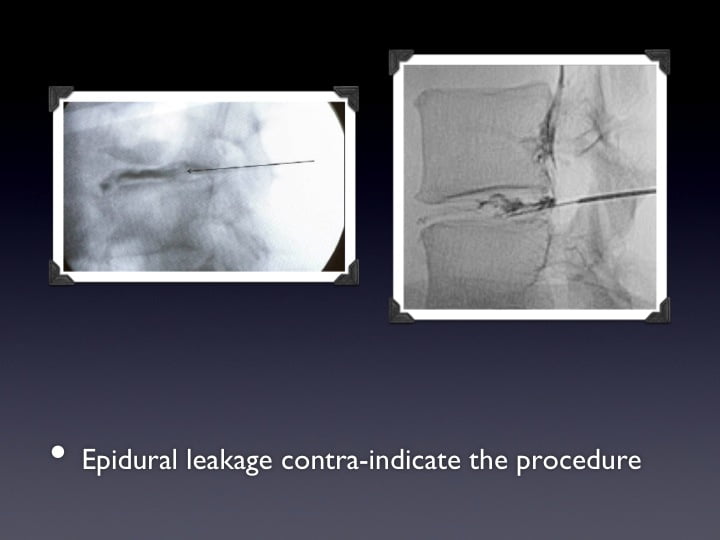

• Herniectomie therapies intra-discales

• Discogel: injection d’alcool gélifié intra-discal

• Herniectomies

• Emanation de PMMA

• Vertebroplasty and schmorl hernia

• Vertébroplastie et arthrodèse rachidienne

• Ostéoplastie et vissage percutanné

• Extraction de fuites de ciment

• Kyphoplastie-vertebroplastie